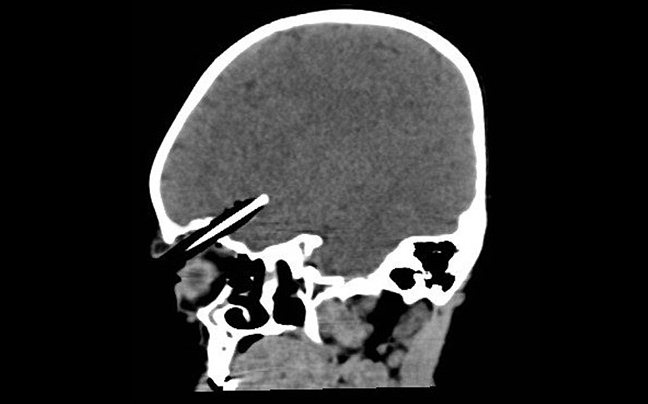

Η μικρή Wren Bowell ήταν άτυχη: καθώς περπατούσε σκόνταψε και έπεσε πάνω στο μολύβι που κρατούσε το οποίο διαπέρασε την κόγχη του ματιού της και «καρφώθηκε» στον εγκέφαλό της.

Ταυτόχρονα η Wren Bowell ήταν πολύ πολύ τυχερή: το μολύβι πέρασε ξυστά από το βολβό του ματιού της και από τρία αιμοφόρα αγγεία και κατέληξε σε βάθος τεσσάρων εκατοστών μέσα στον εγκέφαλό της.

Μεταφέρθηκε εσπευσμένα στο νοσοκομείο του Somerset στη Βρετανία, όπου υποβλήθηκε σε 4ωρη επέμβαση από νευροχειρουργούς για να σωθεί η ζωή της. Μέρος του κρανίου της χρειάστηκε να αφαιρεθεί για να απομακρυνθεί το μολύβι.

Το εντυπωσιακό είναι πως το κοριτσάκι τη γλίτωσε χωρίς κάποια ζημιά στον εγκέφαλο ή τη όρασή!